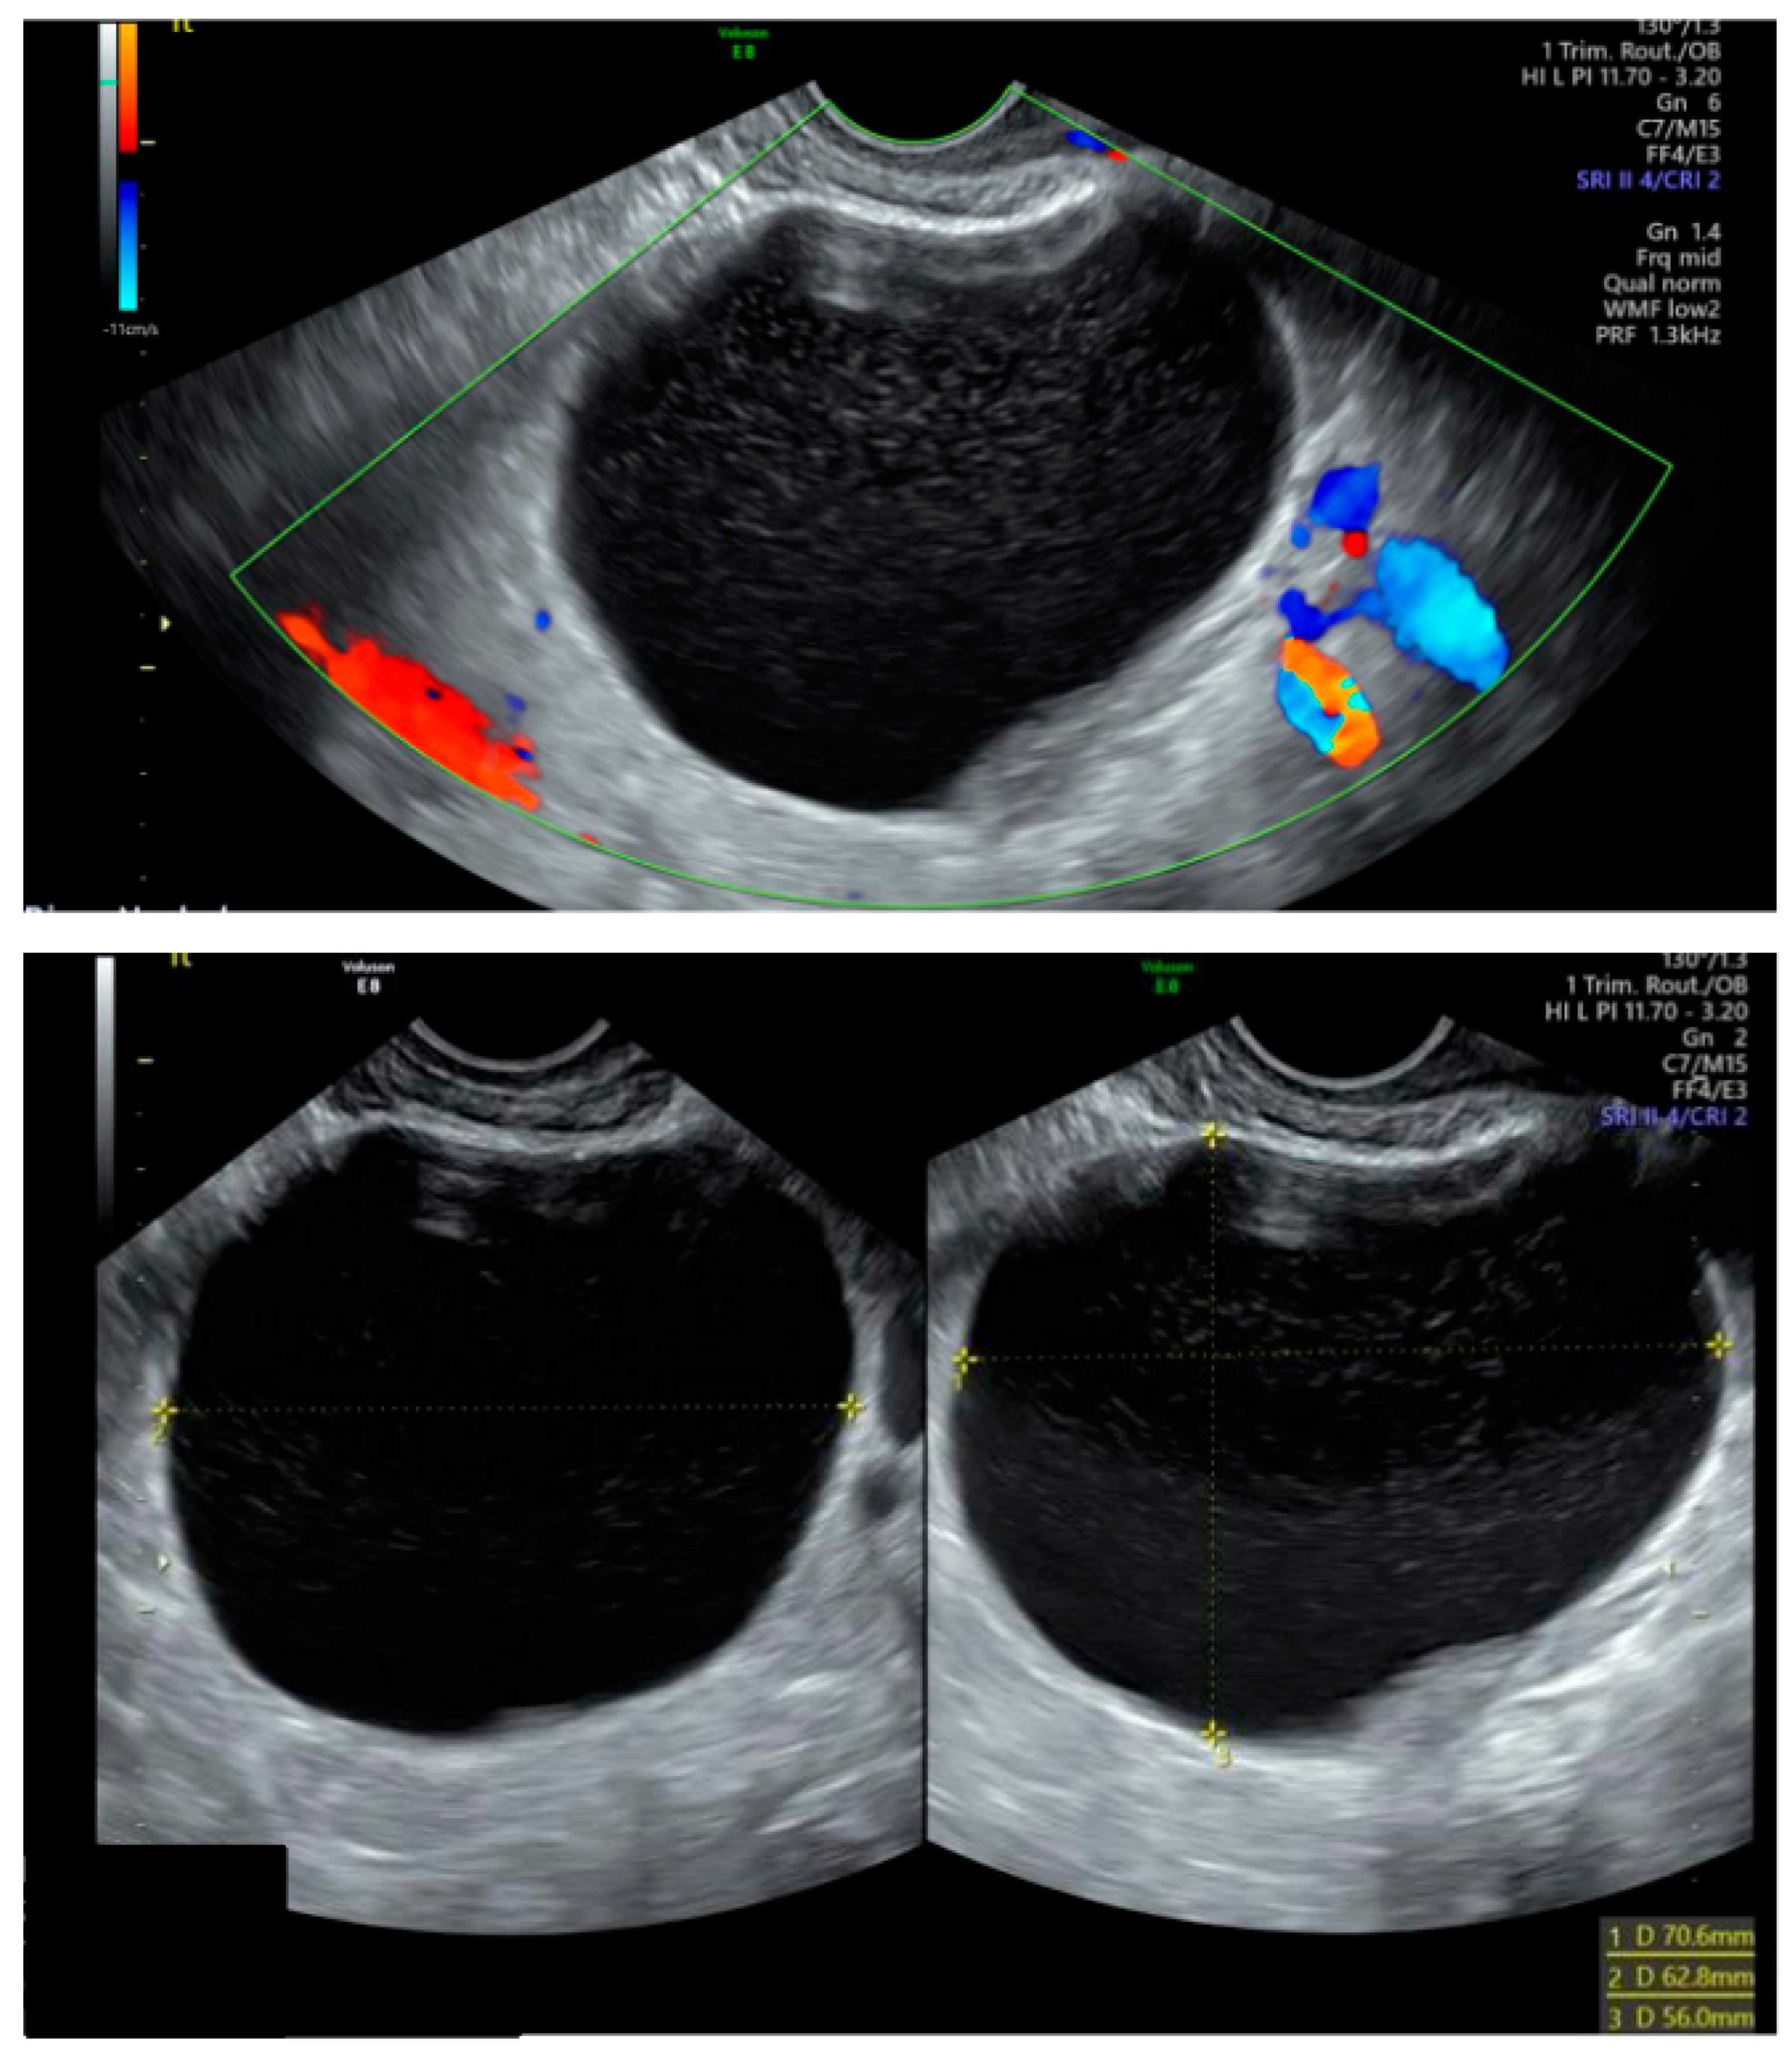

Our case involves a 32-year-old primigravida of Asian origin, who was classified as low-risk during her initial antenatal booking, with normal first-trimester screening results, and presented at 5 weeks’ gestation with lower abdominal pain and light vaginal bleeding. A transvaginal ultrasound confirmed a viable intrauterine pregnancy and identified a 71 × 63 × 56 mm left ovarian cyst with a ground glass appearance, suggestive of an endometriotic cyst (Figure 1). The subsequent anomaly scan at 20 weeks noted a low-lying placenta, fibroids, and an ovarian cyst that remained unchanged in size without exhibiting concerning ultrasonographic features.

Figure 1. Transvaginal appearance of the left ovarian cyst at 5 weeks of gestation.